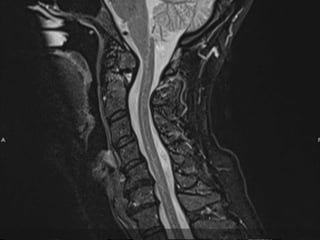

69 year old man with C2

fracture

Admitted for CHF and while

hospitalized was walking to

the bathroom at night and

fell on to head lacerating

forehead. Staff responded

to his calls for help and

immediately ordered a

cervical CT due to

complaints of new neck

pain

PMH: COPD, CHF,

anxiety/dep, liver cirrhosis,

cognitive decline,

pulmonary HTN,

SH: retired lives in group

home

69 year oldman with C2 fracture Admitted for CHF and while hospitalized was walking to the bathroom at night and fell on to head lacerating forehead. Staff responded to his calls for help and immediately ordered a cervical CT due to complaints of new neck pain PMH: COPD, CHF, anxiety/dep, liver cirrhosis, cognitive decline, pulmonary HTN, SH: retired lives in group home